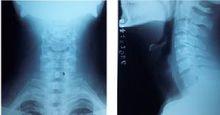

斜位投照方法為患者直立背向胸片架,使身體與暗盒成45°,中心線向頭側傾斜10~20°,對準第四頸椎射入膠片中心,此位置雖然可以顯示小關節、椎間孔及椎弓根情況,但投照中患者難以保證身體絕對不動,從而導致影像效果差,不能清晰顯示椎間孔,直接影響了對患者病情的診斷,且加大了投照工作量。我們對此方法進行了改良,具體做法如下:①將暗盒放在胸片架上,膠片縱長軸中線平行對準胸片架中線。②患者直立站在胸片架前,面向暗盒。雙足稍分開,使身體站穩,轉動身體,使身體的正中面與暗盒成45°,頭向相應的左右前斜方向轉動,使頭的矢狀面與暗盒的平面平行,兩眼平視,頦稍向內收,可使頸椎生理曲度變直,膠片上緣超出枕外隆凸,下緣低於第二胸椎。③中心線對準下頜角下緣垂直射入膠片中心。改良後的投照方法操作簡單,椎弓根及椎間孔顯示清晰,患者站立穩定。因為患者面向膠征身體可以依靠胸片架的支撐,並可手扶胸片架,使物-片距固定,可得清晰有效的影像。工作實踐中,以此方法照出的頸椎雙斜位片,均獲得了良好的影像效果,尤其對老年患者更為實用。